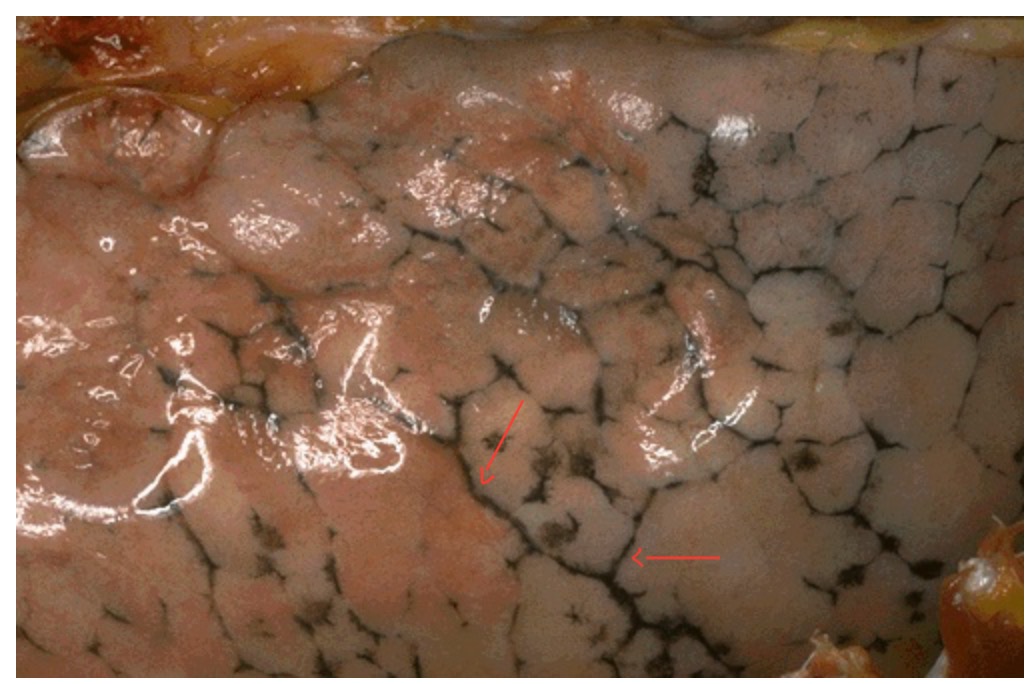

Histological view of the liver full of white or clear droplets. Identify type of intracellular accumulation. Identify the condition and the causes of this condition.

Fat or Lipid Accumulations. Steatosis or Fatty Liver Disease. Causes: Metabolic Diseases (DM Type II, Metabolic Syndrome, & Obesity) & Chronic Alcoholism